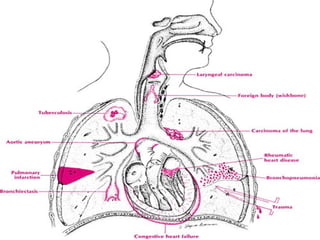

Necrosis

tumoral

Carcinoma

bronquial

Erosión de vasos de

cavidades

adenoma Tuberculosis

pulmonar

Bronquitis

crónica

Bronquiectasia

Rotura de vasos

bronquiales

HEMOPTISIS

Hemorragia por

diapédesis

Estasis pulmonar Estenosis mitral

Insuficiencia cardiaca

Neumonías

bacterianas

Infarto pulmonar

Traumatismos

Aneurisma de aorta

Discrasias sanguíneas

Defectos vasculares

Laceración de vasos del

parénquima

Rotura de aorta

Defectos de

hemostasis

Necrosis tumoral Carcinoma bronquial Erosión de vasosde cavidades adenoma Tuberculosis pulmonar Bronquitis crónica Bronquiectasia Rotura de vasos bronquiales HEMOPTISIS Hemorragia por diapédesis Estasis pulmonar Estenosis mitral Insuficiencia cardiaca Neumonías bacterianas Infarto pulmonar Traumatismos Aneurisma de aorta Discrasias sanguíneas Defectos vasculares Necrosis pulmonar Laceración de vasos del parénquima Rotura de aorta Defectos de hemostasis